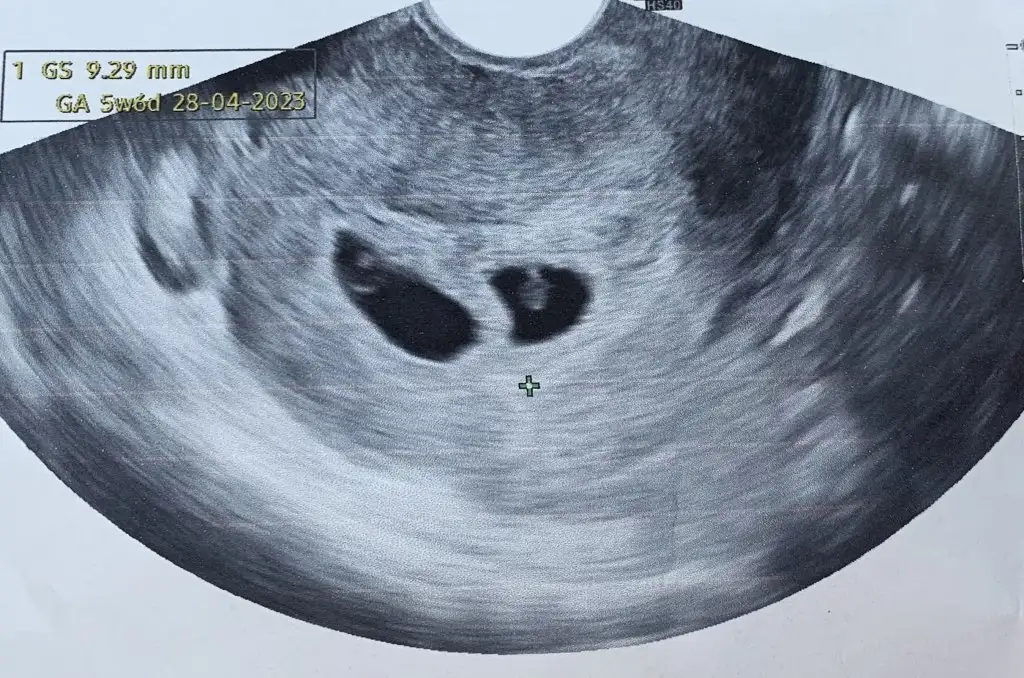

Yaaaa gözün aydın canımmm çok sevindimmmKızlar kesem gorundu cok sukur4+5 diye biliyordum 5+4mus 8cm kese olcumu mu oluyor Eki Görüntüle 3123385

Kesen 0.8 cm olmuşTeşekkürederimcanm.8 cm ne acaba

8 mm dır o herhalde dimiKesen 0.8 cm olmuş![]()